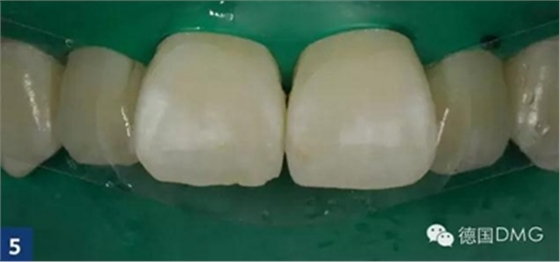

首先, 應(yīng)清潔牙齒或者由您的私人牙醫(yī)為您處理.應(yīng)用橡皮障之后 (Fig. 2),

應(yīng)用icon酸蝕劑酸蝕唇面2分鐘(Fig. 3).

由于最初的酸蝕結(jié)果并不令人滿意,因此我們重復(fù)酸蝕步驟. 利用乙醇干燥之后,可以看到顏色的改變。但是酸蝕結(jié)果還是不滿意,因此我們進(jìn)行了第三次酸蝕。在每一次酸蝕之后, 都應(yīng)將酸蝕劑徹底沖洗干凈然后用icon干燥劑進(jìn)行干燥 (Fig. 4).

然后涂布icon滲透樹脂并靜置3分鐘(Fig. 5), 將多余的材料清除后進(jìn)行光固化 (Fig. 6). 重復(fù)此步驟,靜置時(shí)間縮短為1分鐘.